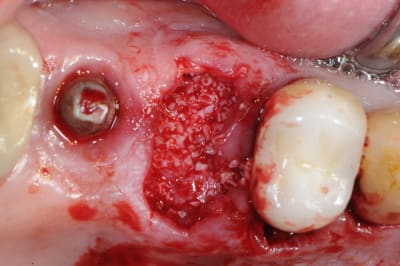

je poursuis donc mon cas clinique si vous voulez bien.

1- curette en appuie sur la face vestibulaire montrant la destruction osseuse.

2- lambeau pleine épaisseur en palatin pour aller chercher un bout de conjonctif qui soit pédiculé.

3 je décole à partit des rebords de la déhiscence osseuse et reste en contacte permanent avec la corticale osseuse tout en décollant la gencive (elle est soulevé donc)

4- comblement avec de la poudre de perlin-pin-pin

( désolé je suis pas au cabinet et je sais plus ce que j'ai mis dedans)

5-6- sutures du conjonctif pour obtenir l'étanchéité (enfin , on essaye)